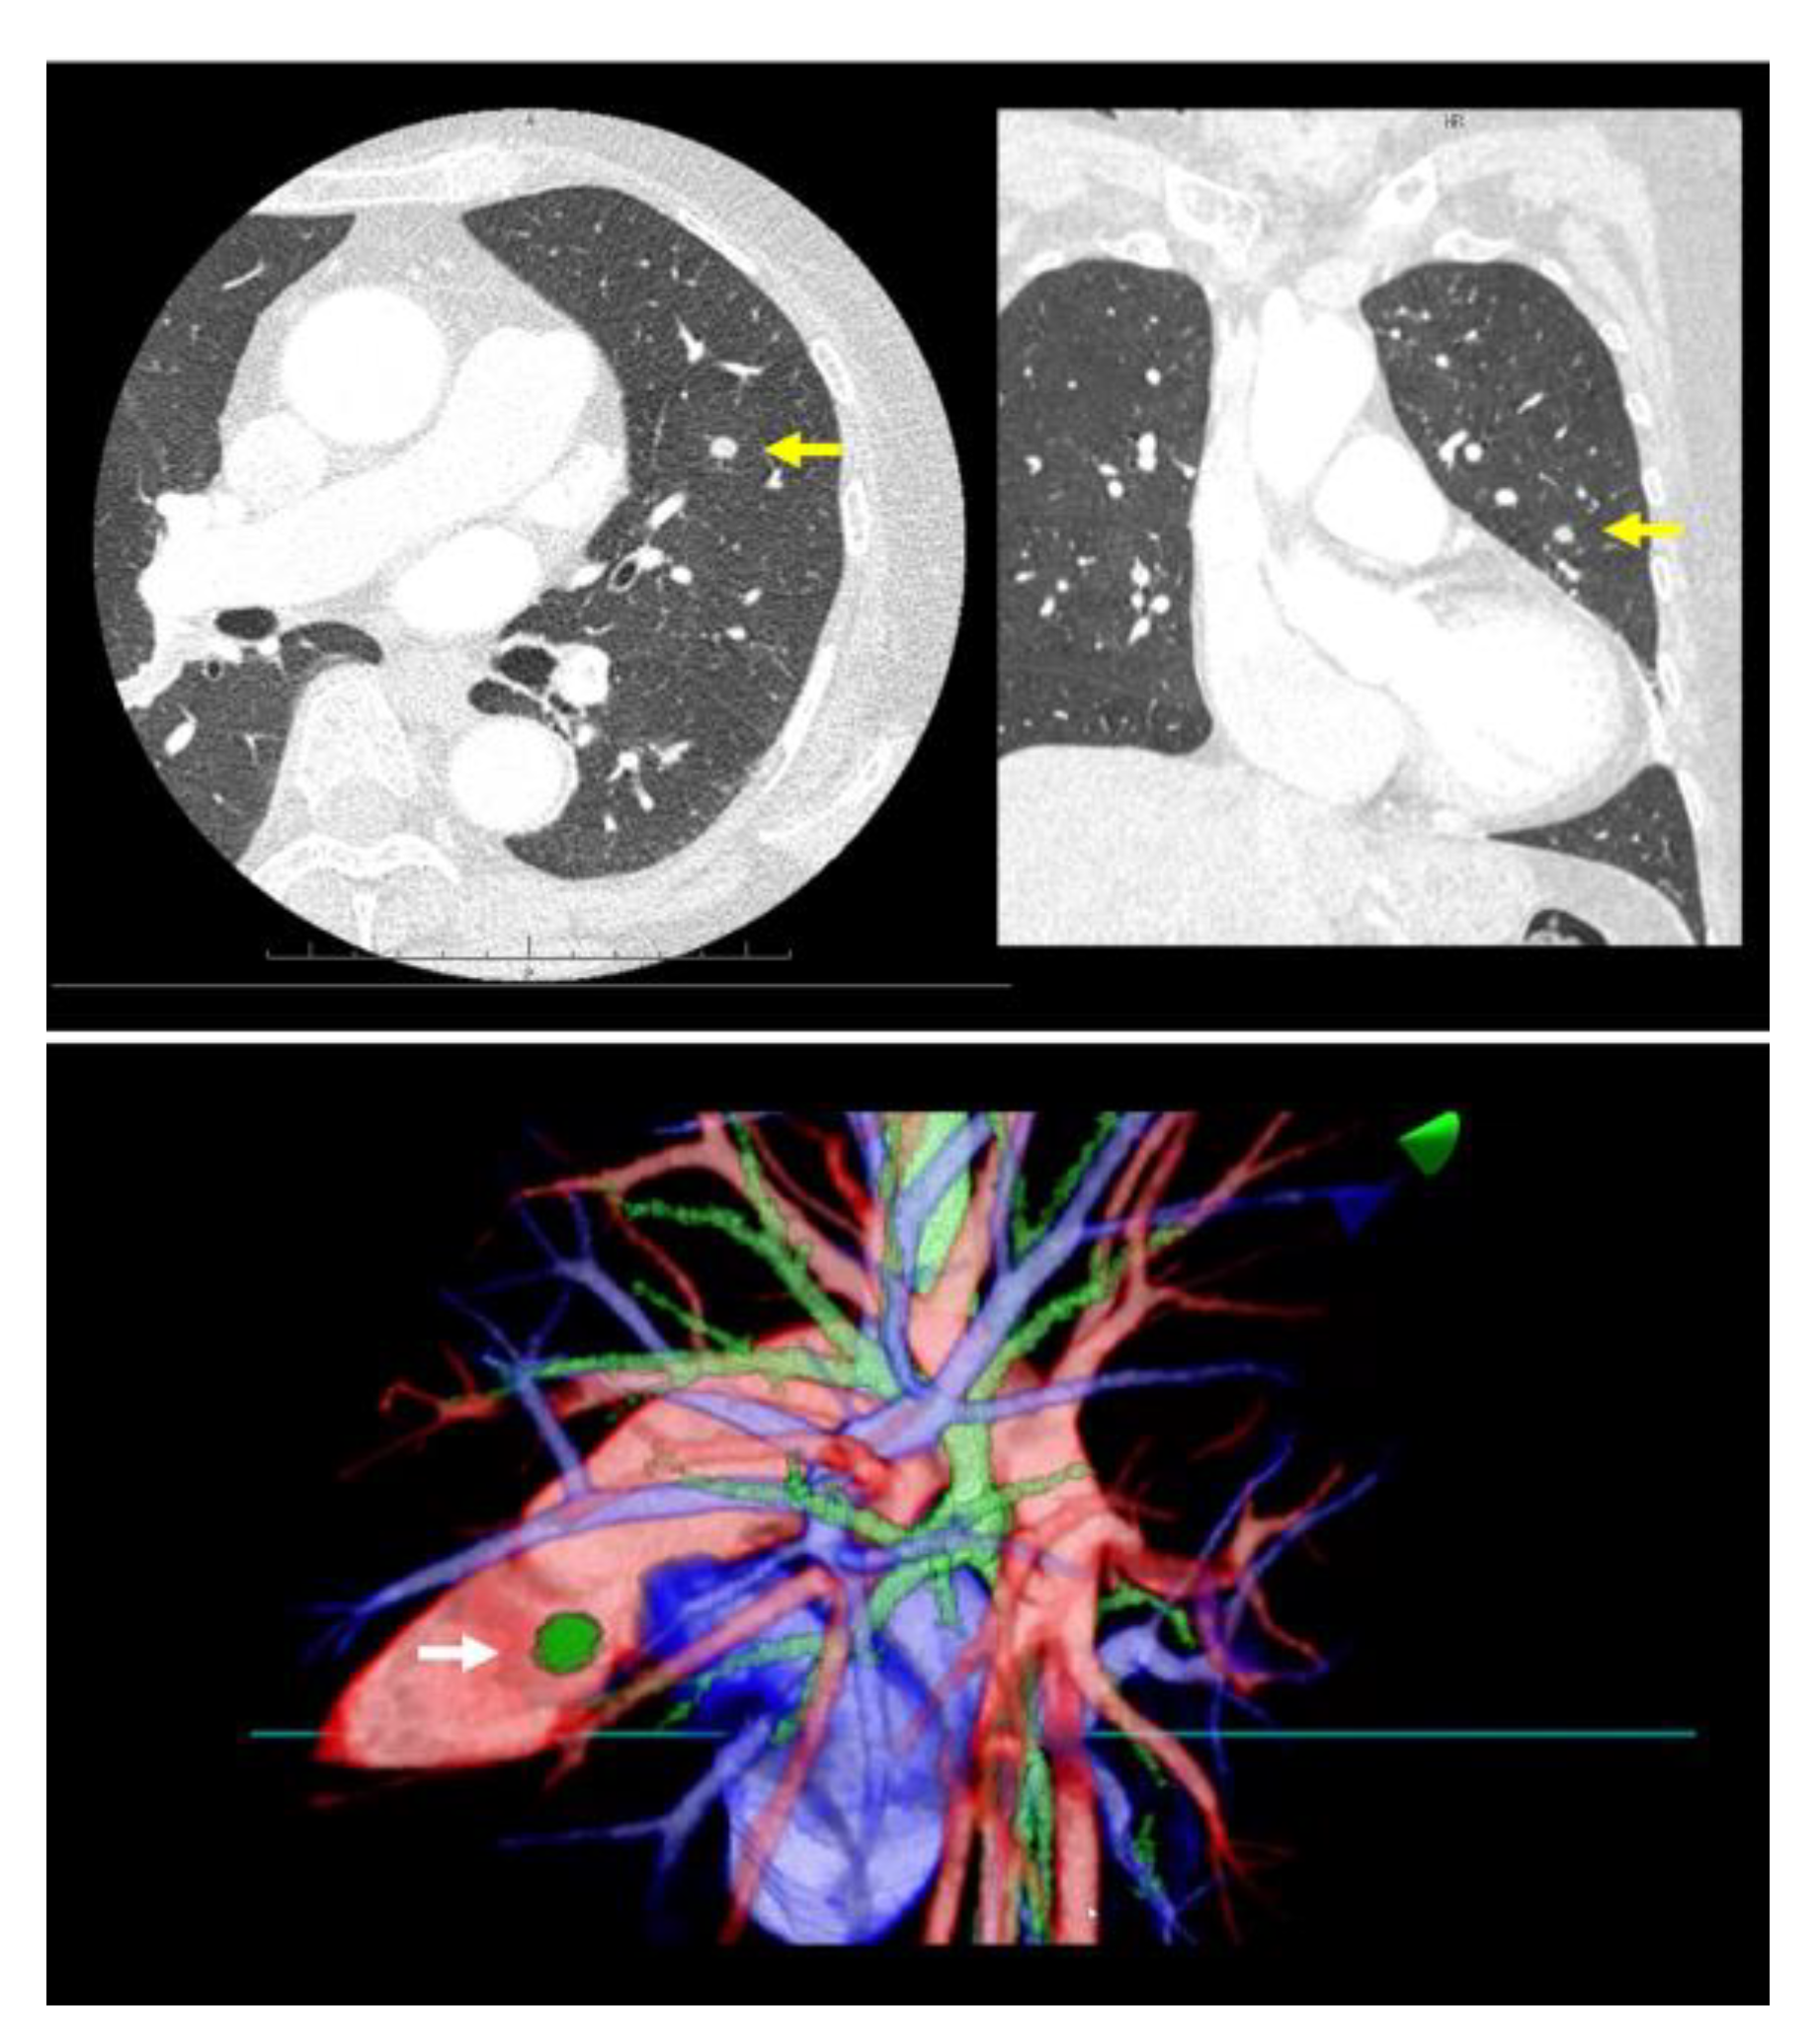

Prior to surgery, a thorough analysis of the surgical resection plan was conducted using patient-specific 3D images. For instance, in a case involving a left lingular tumor, the preoperative chest CT scan and subsequent 3D modeling clearly delineated the tumor’s spatial relationship with surrounding pulmonary structures (as shown in Figure 1). During this review process, the surgeon utilized a HMD to immerse themselves in the virtual reality representation of the patient’s anatomy. The use of hand device controllers enabled the surgeon to interact with the virtual objects in various ways, such as translating, rotating, scaling, cropping, or erasing parts of the model for a detailed examination.

Figure 1.

A virtual dynamic image is meticulously generated from patient-specific three-dimensional computed tomography (3D-CT) data, providing a detailed and interactive representation of the patient’s internal anatomy. The top row of images showcases a preoperative chest CT scan of a patient with a left lingular tumor (yellow arrow). The bottom row of images presents representative views of the 3D model with a left lingular tumor (white arrow) derived from the same CT data.